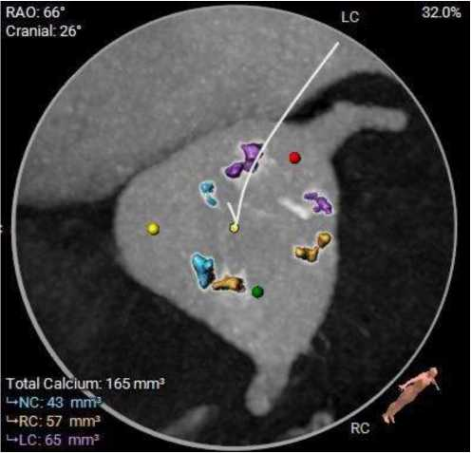

三叶式主动脉瓣,中度钙化,钙化主要分布于瓣叶附着缘及对合缘,钙化分布不均,左冠窦相对较重,右窦和无窦瓣叶对合缘处存在增厚及钙化粘连;

HU850

术前考虑右侧股动脉为主入路,左侧为辅助入路。三叶式主动脉瓣,中度钙化,钙化主要分布于瓣叶附着缘及对合缘,钙化分布不均,瓣膜锚定难度适中,瓣膜植入受瓣叶及钙化挤压存在少量瓣周漏风险。双侧冠脉幵口高度可,左冠切线角度测量瓣叶大于LCA开口下缘到根部距离,结合瓦氏 窦及STJ尺寸预估,冠脉风险适中,建议术中密切灌注左冠灌注情况。水平夹角68度,横位心,主动脉弓宽度、角度尚可,弓部存在散在钙化;左室腔内径偏 大、心室壁稍增厚,心尖部较薄,室壁瘤膨出不排除,建议超硬导丝塑形大一点,注意 不要过度用力顶到心尖部位。外周入路走行迁曲,左侧髂总存在67度锐利夹角,胸主和右侧髂总存在少量散在钙化, 血管内径可,血管内壁存在钙化和不规则纤维增厚,入路穿刺规范操作,小心通过,避免入路血管损伤及相关并发症。为避免手术并发症,手术预装AV29瓣膜,根据23mm球囊预扩结果选择瓣膜型号,计划瓣环下零位幵始释放。